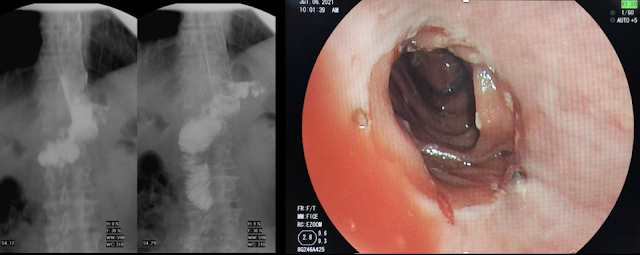

Se decidió iniciar cobertura antibiótica con piperacilina/tazobactam, NPT y solicitar exámenes de imagen. La tomografía reveló falta de continuidad y afrontamiento de anastomosis esófago-yeyunal con separación de suturas metálicas, asociado a pequeñas colecciones adyacentes con contenido aéreo y, el tránsito intestinal mostró fuga de contraste hacia hipocondrio derecho con trayecto de salida hacia dren y bolsa colectora.